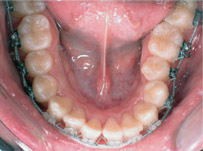

齒列擁擠的不正咬合經由擴大效果排列整齊:

Before

Proceeding

After